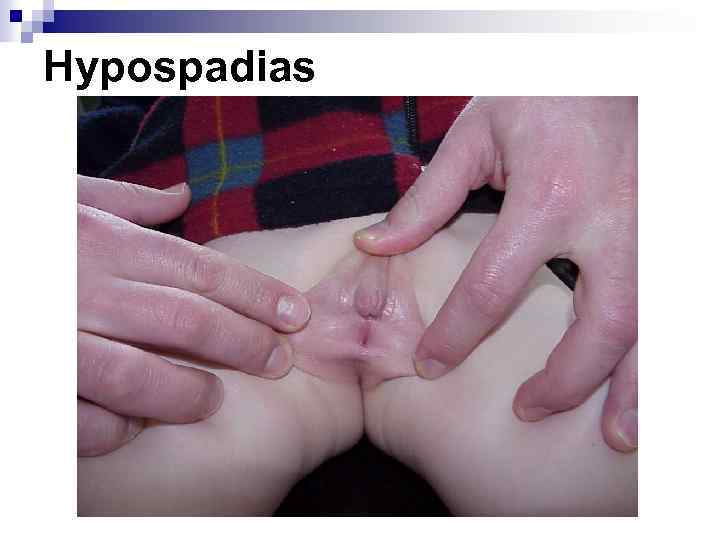

Hypospadias

Hypospadias